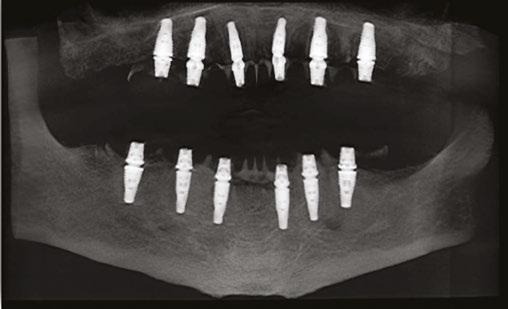

The protocol for immediate loading of fullarch implants includes the extraction of all non-salvageable teeth, implant placements, abutment placements, intraoral scans (Itero®) with scan bodies placed on the abutments, and in-house milling (Zirconzahn®) on the day of the surgery. The information referred to the esthetics, and vertical dimension is gathered with the extraoral 3D facial scans with Face Hunter software (Zirconzahn), 2D photographs, and intraoral scans prior to surgery. The day of extractions and implant surgery, abutments are placed and scanned, and initial designs are merged with anatomical landmarks. The polymethyl methacrylate (PMMA) prosthesis is milled in-house following the merging of the initial and post-implant placement digital scans and the design of the new teeth the day of the surgery.

The day of the surgery, intraoral markers are placed, and intraoral scans are captured prior to surgery. The remaining teeth are extracted, implants and muti-unit abutments (Neodent®, Straumann) are placed (Figure 5), and abutment scan bodies

get connected. Intraoral scans are done again after the surgery (Figure 6), and pre- and post-surgery scans are overlapped to mill the PMMA teeth the day of the surgery. While I do own a 3D printer, I like milled PMMAs more since that provides more shade options with the lighter colors. I also find milled PMMAs are stronger than the printed PMMAs.

PMMA gets milled (Figure 7) and delivered the day of the surgery with a very passive fit (Figures 8 and 9).